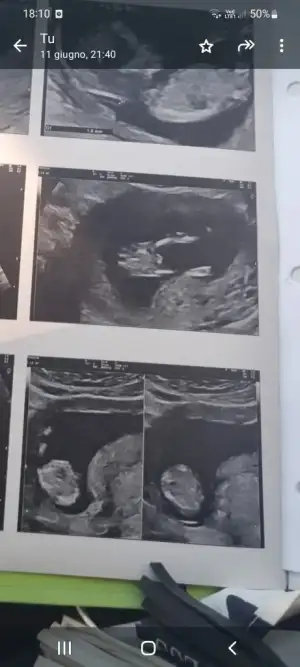

Cinsiyet tahmini

Kız gibi geldi bana sağlıkla gelsınMrb bebegimin cinsiyetini merak ediyorum bilen var mi acaba???

Baya erkek gibi duruyorMrb bebegimin cinsiyetini merak ediyorum bilen var mi acaba???

Bana da oyle geliyo ama bi turlu emin olamiyorumBaya erkek gibi duruyor

2 bacak arasından bakıyorlar attığın fotoğrafta o kısım da var çıkıntı var orada sadece ben mi görüyorumBana da oyle geliyo ama bi turlu emin olamiyorum

Erkek benceMrb bebegimin cinsiyetini merak ediyorum bilen var mi acaba???